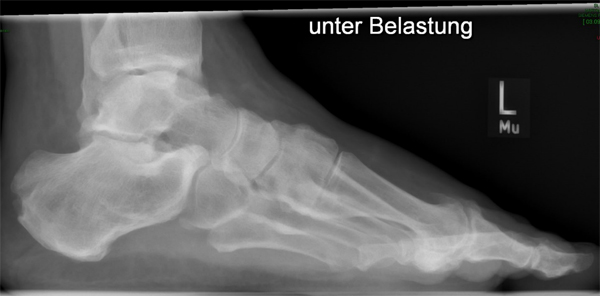

• Belastete Röntgenaufnahmen in 3 Ebenen.

• Evtl. Fotodokumentation der Exostosen.